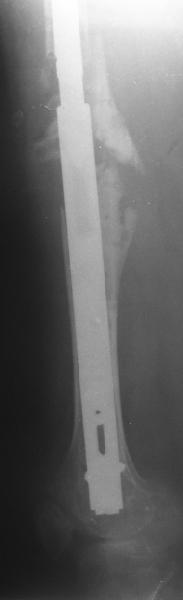

Female, rheumatoid, THA in 2003, car accident in 2006, failed plating. Nailing in Oct 2007. The nail is solid with hollow proximal part where the stem is docked. Last images are in 1 year after

nailing.

THX for the discussion. After few days of traction by ex-fix the surgery was performed. An attempt of closed nailing was unsuccesful because of fragment translation, which was blocked by cement fragments. After removal of broken cement pieces reduction was reached "automagically". Also some cement from lateral part was removed by

chisel to expose distal 40-50 mm of the stem to allow tight fit of the nail. Further fixation by the nail was pretty easy and straightforward. Images attached. The stem looked stable in its proximal part both laterally and medially. Comments/critics are welcome.